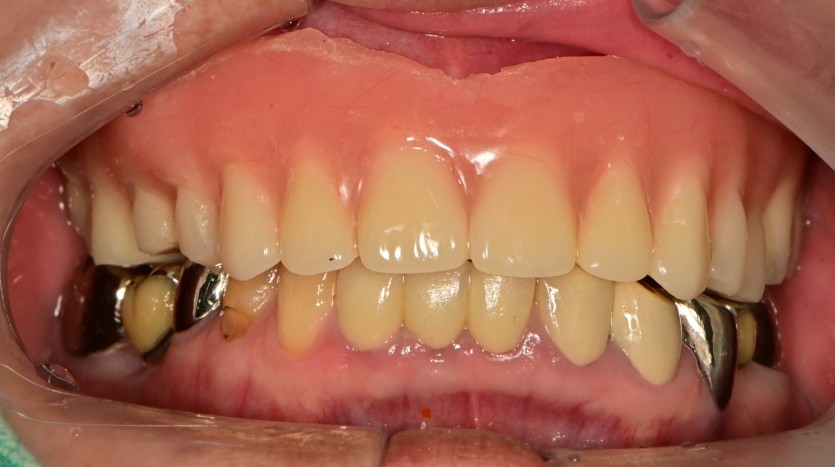

만 80세 상악 전체 임플란트 증례

상악 전체 임플란트 증례입니다.

9개의 임플란트로 완성하였습니다.